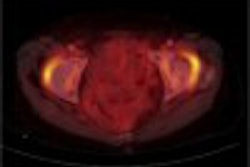

Under the agreement, Chicago-based Miicro will conduct PET imaging studies for GSK, assisting in drug development efforts. Work on the first of these studies for GSK is in progress, according to Miicro.